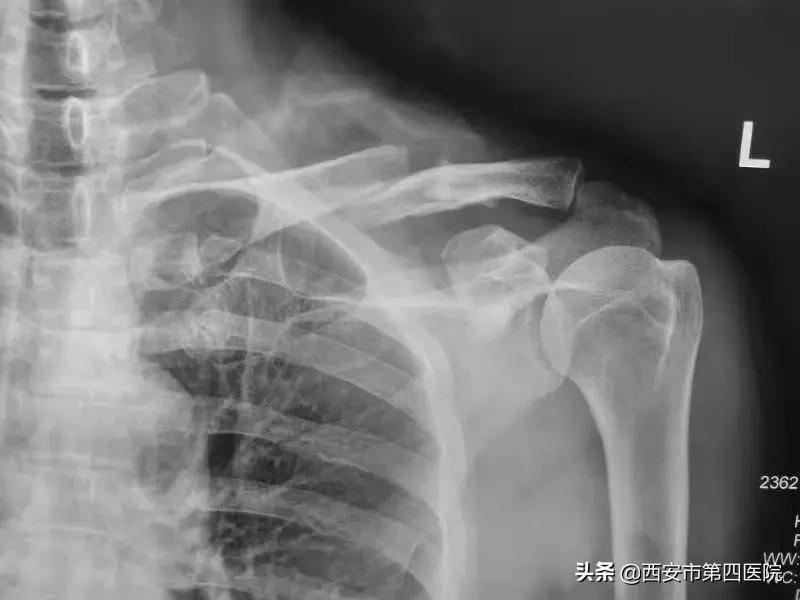

患者宋某,因摔倒致左侧肩关节疼痛伴活动障碍1天,去大差市院区就诊,姬海鹏副主任医师接诊,经过详细询问病史及体格检查后,考虑为左侧锁骨骨折,X线片结果证实了专家的诊断。与家属沟通并征得知情同意后,在医院领导及综合办的协助下,患者当天即入住航天城院区过渡病房。

锁骨骨折是比较常见的骨折。对于移位比较明显的锁骨骨折,目前多数学者建议行切开复位内固定治疗。但由于需要注意的细节繁杂,锁骨上皮神经对其支配的区域影响常被低估,医源性的锁骨上皮神经损伤时有发生,尤其对于女患者,很可能造成乳腺部分区域感觉缺失,从而给患者带来生理和心里的双重打击。